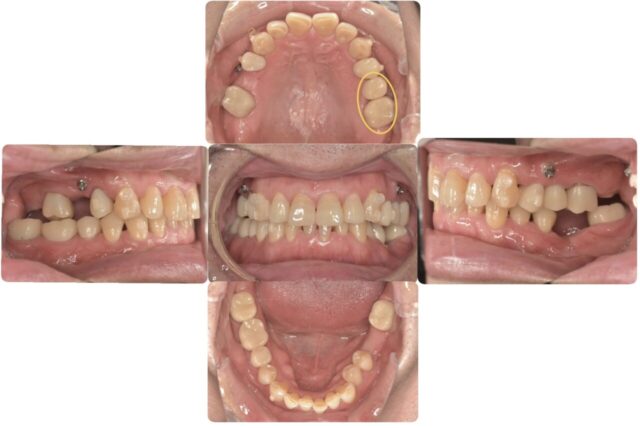

まずはレントゲン写真と口腔内写真をご覧下さい。

この写真を見て何か違和感を感じませんか?

よく見ると、奥歯にばかり治療歴があります。

実はこの方の歯が悪くなる原因は噛み合わせにあります。

正面からのかみ合わせを見た時、下の歯がほとんど見えませんこれは「ディープバイト」と言ってよくない歯並びである不正咬合の一つです。

本来、人は上下の顎の前後運動により奥歯にかかる圧を抜いてバランスを保っています。しかしこのかみ合わせは前後に擦り合わせるスペースがないため、奥歯がずっと噛み合ったままの状態です。そのため、奥歯にばかり負担がかかり、ヒビが入ってきてしまったり、治療をして詰め物をしても取れてしまったりしてくるのです。これを治すにはかみ合わせのバランスを整える、つまり「矯正」が必要になります。